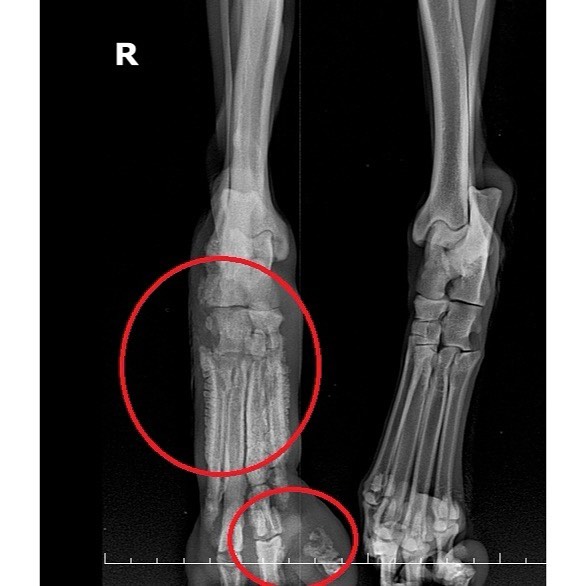

¾È³ç Çüµé! ¿À´Ã ¼Ò°³ÇÒ ¾ÆÀÌ´Â µ£¿¡ °É·Á º´¿ø¿¡ ¿À°Ô µÈ ´ó´óÀ̸¦ ¼Ò°³Çغ¸·Á°í ÇØ. À̸§Àº ¾ÆÅ°ÄÚ! »óŰ¡ ½É°¢Çؼ ±¸Á¶ Ä¡·á°¡ Àý½ÇÇÑ »óȲÀ̾ú¾î. £¨º¸È£¼Ò¿¡¼ ¸· µµÂøÇßÀ» ¶§ »çÁøÀÓ£© Áö³ 10¿ù 14ÀÏ, ±¸Á¶µÇ¾î ¿ì¸® º´¿øÀ¸·Î ¿Ô°í, ´ç½Ã ¹ß°¡¶ô »À°¡ ¸¹ÀÌ ³ì¾ÆÀÖ¾ú°í, °ñ¼ö¿°µµ ¸Å¿ì ½ÉÇÑ »óÅ¿´¾î. £¨ »À°¡ ´Ù º¸ÀÏ Á¤µµ ¤Ð¤Ð£© Å»¼ö¿Í ¿µ¾ç½ÇÁ¶µµ ¸Å¿ì ½ÉÇß°í, ½ÉÀå»ç»óÃæµµ °¨¿°µÇ¾îÀÖ¾ú°í, üÁßµµ ³Ê¹« Àû°Ô ³ª°¬¾î..¤Ð ¤Ð Åп¡ º¯/¼Òº¯ ¶§¹®ÀÎÁö ³¿»õ°¡ ½ÉÇØ¼ ¸ñ¿åµµ 3¹ø Çß³ß! ±×·¡µµ °£/½ÅÀå µî Àå±â ¹× Àü¹ÝÀûÀÎ °Ç°»óÅ´ ±¦Âú¾Ò¾î. º´¿ø¿¡ ¿Â ´çÀÏ ¾à+ĵ+»ç·á ÇÏÆ® ºñºö¹äÀ» ¸¸µé¾îÁÖ¾ú´Âµ¥, ¿ÏÀü Çã°ÌÁö°Ì ¸Ô´õ¶ó ¤Ð¤Ð ¤Ð¤Ð¤Ð ¤Ð ¿ÏÀü ¼ø»è ¤§¤§ ÀÌ·¸°Ô º´¿ø¿¡¼ ¾à 1ÁÖÀϰ£ ¼ö¾× ¹× ¿µ¾çº¸Ãæ Çß¾î. £¨¾ÆÅ°ÄÚ ÁøÂ¥ ÁøÂ¥·ç ¾äÀüÇϰí ÂøÇØ ¤Ð¤Ð£© ±×¸®°í Áö³ 10¿ù 22ÀÏ, ¿ìÃø µÞ´Ù¸® ÀûÃâ ¼ö¼úÀ» ¹Þ¾Ò¾î. °í°üÀýºÎÅÍ ´Ù¸® Àüü¸¦ ¸öÅë¿¡¼ ºÐ¸®ÇÏ¿© ¶¼¾î³Â¾î. Å« ¼ö¼úÀ̾ú´Âµ¥ ¾ÆÅ°ÄÚµµ Àß ¹öÅßÁÖ¾ú°í, ¾ÆÇà ÅÙµ¥ ¹äµµ Àß ¸Ô¾îÁ༠¾ó¸¶³ª »ÑµíÇÏ°í °í¸¶¿ü´ÂÁö ¸ô¶ó. µÞ´Ù¸® ÀýÁ¦¼úÀÇ ¸î ¾ÈµÇ´Â ¼úÈÄ ¹ß»ýÇÏ´Â ¹®Á¦ Áß Çϳª°¡, ¼ö¼ú ºÎÀ§¿¡ ¿°ÁõÀ̳ª ¾×ü°¡ Â÷´Â °ÍÀε¥ ±×·± °Í ¾øÀÌ Á¤¸» Àß È¸º¹Çß¾î!! ³Ê¹« ¸¶¸£°í ±ÙÀ°ÀÌ ¸¹ÀÌ À§ÃàµÇ¾îÀÖ¾î¼ °ÆÁ¤Çߴµ¥, ´ÙÇàÈ÷ Àß À̰ܳ»ÁÖ¾ú¾î. £¨Àß °È°í, Àß ¶Ù¾î!£© ¾î´ÀÁ¤µµ ȸº¹ÇÑ ¾ÆÅ°ÄÚ´Â ¿ù¿äÀÏÀÎ ±×Àú²² ÀÓº¸Ã³·Î À̵¿Çߴµ¥, ³Ê¹«³Ê¹« ±Í¿±Áö ¾Ê¾Æ? ¾ÆÅ°ÄÚ´Â ¹Ì±¹ ÅØ»ç½º·Î ÇØ¿Ü ÀÔ¾ç °¥ ¿¹Á¤À̶ó°í ÇØ! ³Ñ³Ñ Àß µÆÁö ¤Ð¤Ð¤Ð ÇÏÁö¸¸ ÅØ»ç½º·Î °¡´Â ÇØ¿ÜÀ̵¿ºÀ»çÀÚ´Â ¾ÆÁ÷ ¸ø ±¸Çß´Ù°í Çϴµ¥... Ȥ½Ã ³»³â 1¿ù ¹Ì±¹À¸·Î °¡´Â Çü ÀÖÀ¸¸é ÂÊÁö ºÎÅ¹ÇØ!! ¾ÆÅ°ÄÚ ÀÌÁ¦ º¸È£¼Ò°¡ ¾Æ´Ñ, µû¶æÇÑ Áý¿¡ »ì°Ô µÇ¾î¼ ³Ê¹«³Ê¹« ´ÙÇàÀÌÁö ¤Ð¤Ð!! Å« ¼ö¼úµµ À̰ܳ»°í, °í»ý ¸¹¾Ò¾î! ±×·³ Á¶¸¸°£ ¶Ç º¸ÀÚ »ç¶ûÇØ ¤Ð¤Ð¤Ð